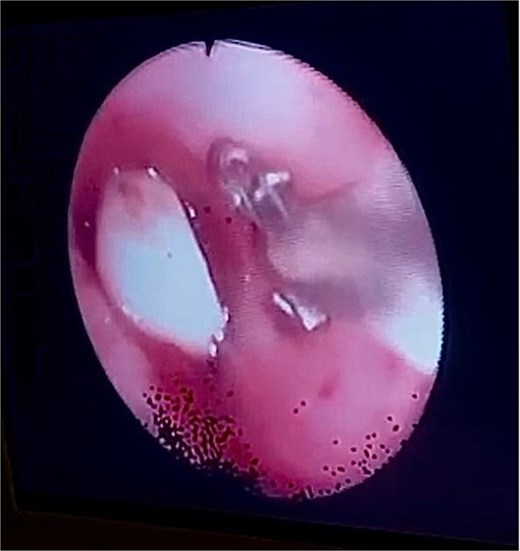

After obtaining informed and written consent, an emergency fiberoptic bronchoscopy was performed in the ICU on 20 October 2022. During the procedure, a FB was visualized at the origin of left mainstem bronchus. The decision was to extract the FB using endobronchial basket. However, the basket could not be deployed and opened in the left main bronchus due to the small size of the bronchus. To address this issue, the team utilized an endoscopic retrograde cholangiopancreatography (ERCP) balloon to mobilize the dental bridge from the left mainstem bronchus to the carina, facilitating the removal of the FB. Following that, the endobronchial basket was passed and opened to capture the dental bridge.

Following the procedure, the patient underwent a percutaneous tracheostomy and was gradually weaned off the mechanical ventilator. After a 2-month stay in the ICU, the patient was discharged to a rehabilitation center for further recovery (Figs 2 and 3).

Bronchoscopy view showing the dental bridge lodged in the left mainstem bronchus.